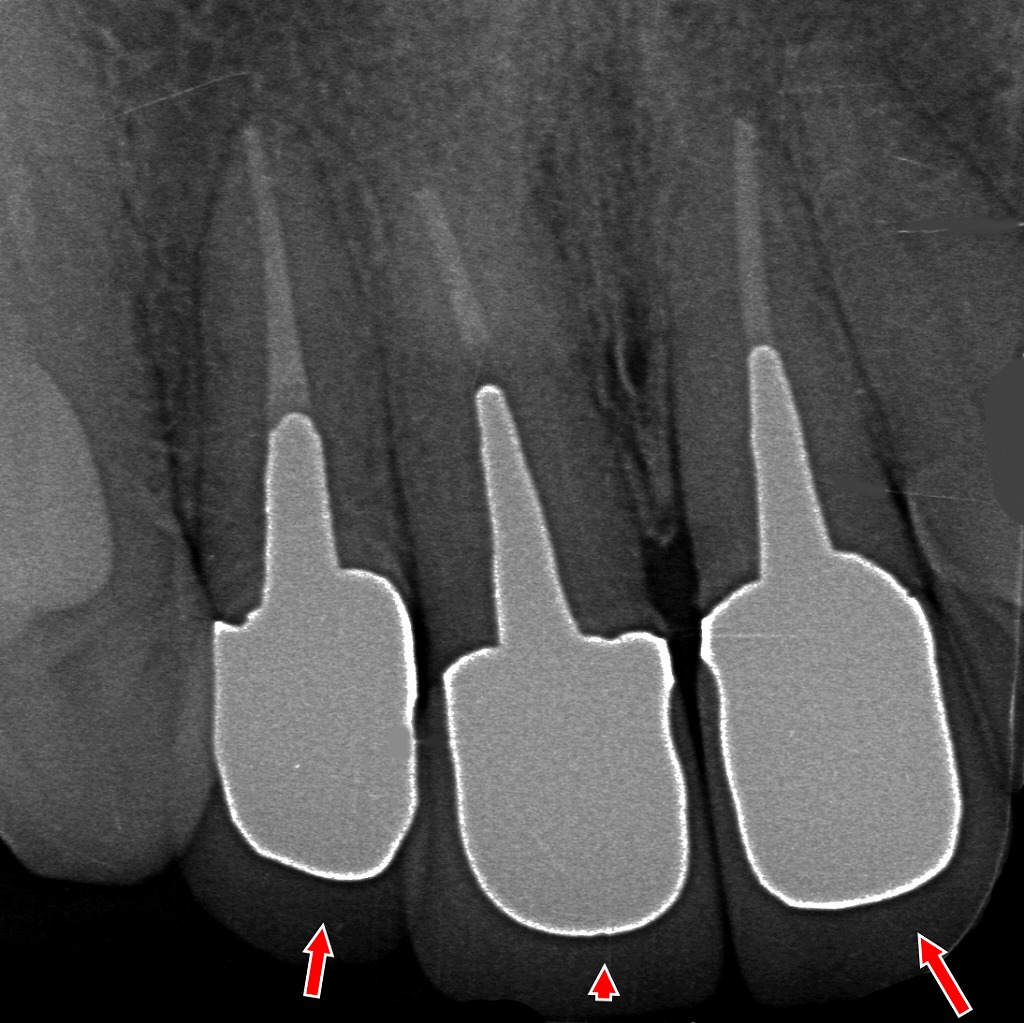

■ 画像の解説

このデンタルX線画像では、前歯3本に新しく作製したメタルボンドクラウン(メタルセラミック)が装着された状態が確認できます。

矢印の部位は、歯根周囲の骨の状態やフィットを示しています。

特徴的な所見:

- 各歯にメタルコアが再度築造され、適正な長さで根管内に位置している

- クラウン外形は均一で、マージン適合も良好

- 歯根周囲には透過像の異常(炎症・破折線)を認めない

- 3本とも支台歯としての形態が安定し、補綴物を支える十分な保持力が確保されている

前回の「歯根破折・クラウン破折」の状態から、支台歯を適切に再評価し、新しいメタルボンドクラウンとして再補綴した仕上がりです。